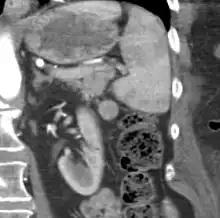

CT scan of an accessory spleen (circular object in center of image) between the spleen and left kidney.

An accessory spleen is a small nodule of splenic tissue found apart from the main body of the spleen. Accessory spleens are found in approximately 10 percent of the population[1] and are typically around 1 centimetre in diameter. They may resemble a lymph node or a small spleen. They form either by the result of developmental anomalies or trauma.[2] They are medically significant in that they may result in interpretation errors in diagnostic imaging[2] or continued symptoms after therapeutic splenectomy.[1] Polysplenia is the presence of multiple accessory spleens rather than one normal spleen.

If splenectomy is performed for conditions in which blood cells are sequestered in the spleen, failure to remove accessory spleens may result in the failure of the condition to resolve.[1] During medical imaging, accessory spleens may be confused for enlarged lymph nodes or neoplastic growth in the tail of the pancreas,[5] gastrointestinal tract, adrenal glands or gonads.[2]